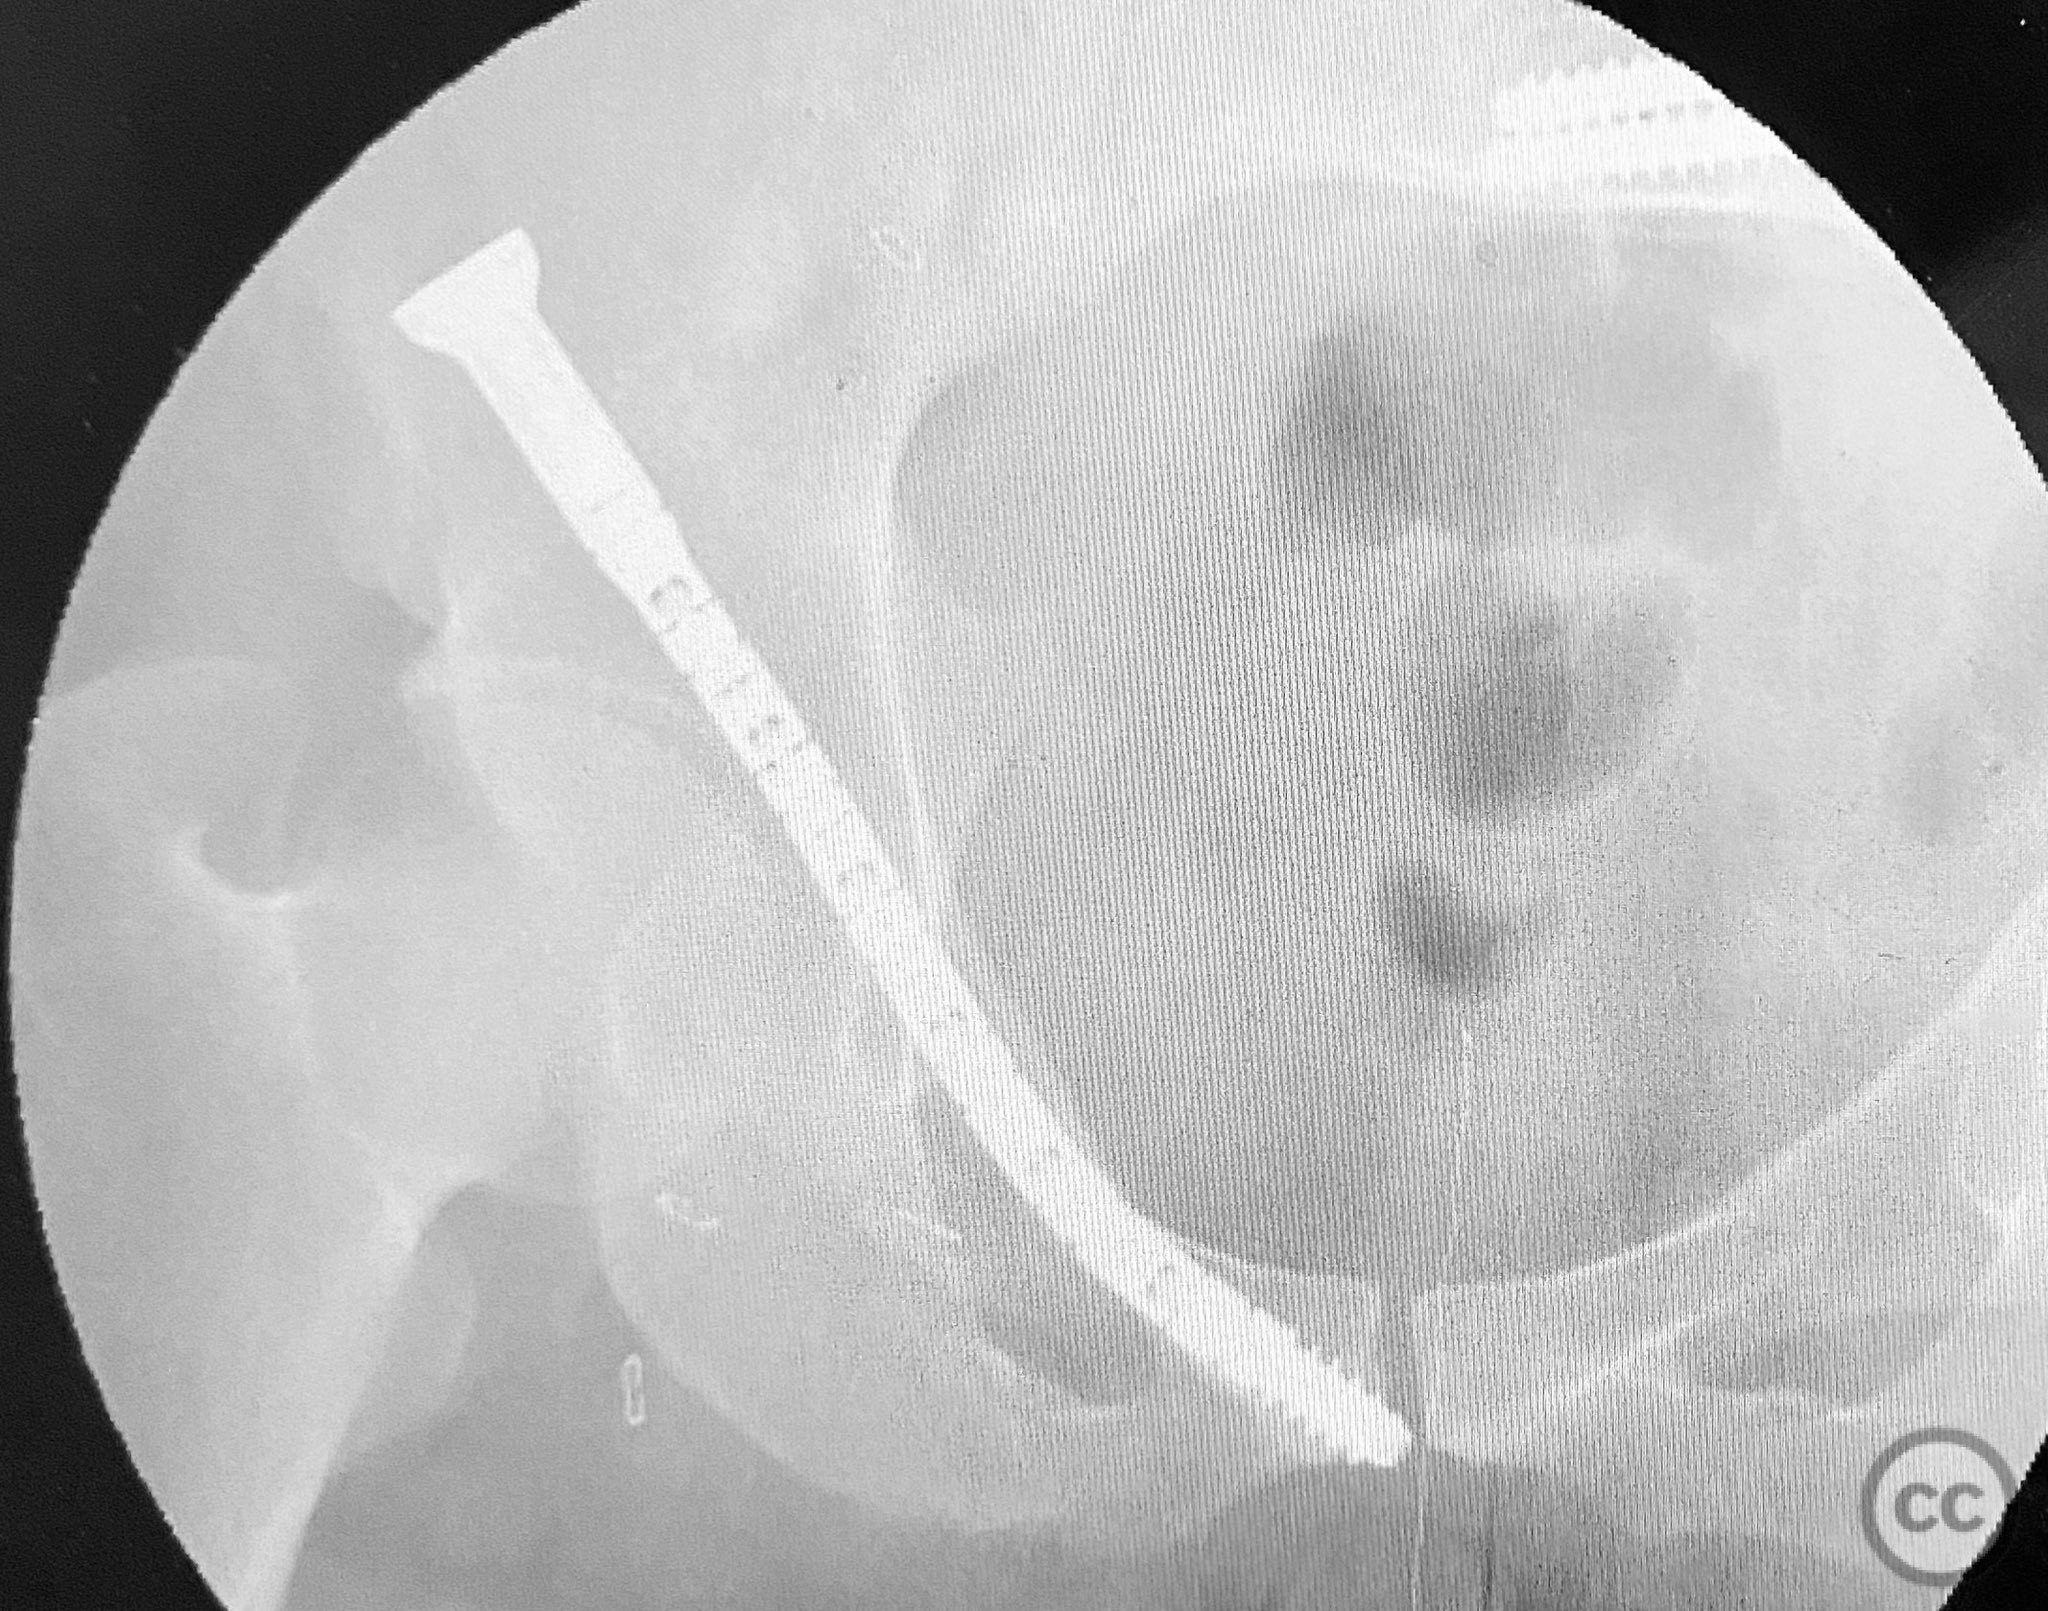

Clinical and radiological findings:  A patient presented with pelvic ring instability and deformity secondary to a left sacral fracture and a right pubic ramus fracture. Imaging demonstrated a displaced left sacral fracture (AO/OTA 61-C1.3) and a right superior pubic ramus fracture, with associated pelvic ring deformity. No neurovascular compromise was noted on initial assessment.

Anatomical surgical approach:  A percutaneous approach was utilized. After standard preparation and draping, a small incision was made over the entry point of the right superior pubic ramus. The near cortex was prepared in routine fashion. A curved guide was introduced along the intramedullary pathway of the superior pubic ramus, followed by measurement of required device length. Sequential reaming was performed: first with an opening reamer, then with a pathway reamer to accommodate the device trajectory. The insertion guide wire was exchanged into position, and the CurvaFix device was inserted along the prepared pathway. The device was then locked to achieve rigid fixation.

The application of the CurvaFix device was straightforward. Preparation of the near pathway, insertion of the curved guide, length measurement, reaming, and device insertion proceeded without technical difficulty. The device demonstrated rigid fixation upon locking, even in the presence of comminution at the fracture site.

Orthopaedic implants used:   CurvaFix 130mm length / 7.5mm diameter intramedullary device